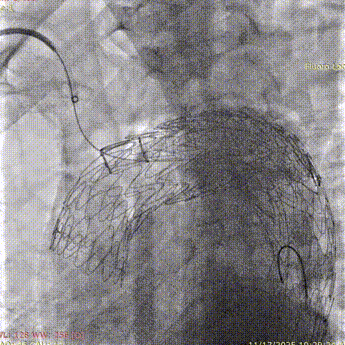

9. 进行主动脉弓部及头部造影,瘤体未见显影,双侧血流通畅,效果满意。

斑马导丝是治疗什么的「胸有乾坤」至简至易 行之有效—— Zone 0 TBE植入治疗弓部动脉瘤病例报道_https://www.jmylbn.com_新闻资讯_第24张

斑马导丝是治疗什么的「胸有乾坤」至简至易 行之有效—— Zone 0 TBE植入治疗弓部动脉瘤病例报道_https://www.jmylbn.com_新闻资讯_第25张

10  LSA根部弹簧圈栓塞。

术后随访

术后复查CTA显示支架形态良好,瘤体感觉完全,弓上分支血管显影通畅,效果满意。